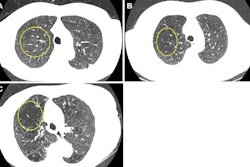

The Landy team sought to identify low-risk individuals in the NLST and estimate how many lung cancers would have been delayed one year in diagnosis had people been assigned to biennial screening. The group used three methods to attempt to predict whether an individual would be a good candidate for biennial lung cancer screening: a recalibrated lung cancer prediction convolutional neural network (LCP-CNN); the lung cancer risk assessment tool (LCRAT + CT), a statistical model combining individual risk factors and LDCT image features; and the American College of Radiology's (ACR) Lung-RADS version 1.1 metric for lung nodules.

The study included 10,831 LDCT images from patients with presumed nonmalignant lung nodules. Of these, 195 were diagnosed with lung cancer at follow-up screening. The researchers found that recalibrated LCP-CNN had the highest performance of the three methods.